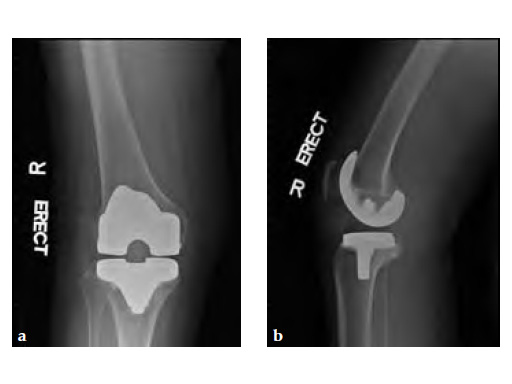

Case 2: A 76-year-old female underwent right total knee replacement 5 years ago and left total knee replacement 4.5 years ago

The patient underwent left L5S1 minimally invasive TLIF with pedicle screws 2 years ago for left lumbar 5th radiculopathy. At the same time she was put on fosamax for osteoporosis.

Based on the negative MRI thigh and positive MRI lumbar spine of multiple levels of spinal stenosis, the patient underwent epidural analgesic injection. Patient sustained right femur midshaft periprosthetic fracture the next day after her epidural injection with no trauma.